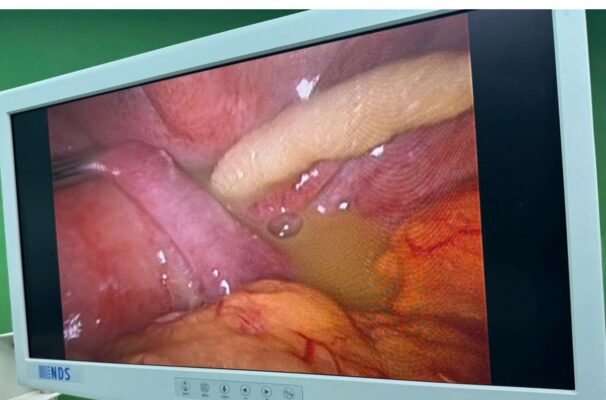

Kíp trực khoa Ngoại chung phối hợp khoa Gây mê hồi sức đã tiến hành phẫu thuật cấp cứu nội soi ổ bụng xử lý tổn thương. Qua nội soi ổ bụng được thực hiện, cho thấy vùng hố chậu trái có dịch đục, mùi hôi nhẹ, lượng trung bình (~200 ml). Mạc nối lớn bám tụ về vùng hố chậu trái, mô viêm dính quanh đại tràng sigma. Tại vị trí đại tràng sigma, phát hiện lỗ thủng đang xì phân, mô ruột phù nề, dính chặt. Dị vật không dễ bộc lộ qua nội soi do nằm sâu và đâm xuyên thành ruột. Đây là một trường hợp bệnh hy hữu, tiên lượng rất nặng do vị trí thủng ở đại tràng, thời gian đến viện muộn, dị vật có tính chất phức tạp. Các phẫu thuật viên quyết định chuyển mổ mở đường trắng giữa trên dưới rốn. Tiến hành bóc tách đại tràng sigma cẩn thận, phát hiện hàm răng giả nguyên khối có hai móc kim loại sắc nhọn xuyên qua thành đại tràng sigma. Dị vật được lấy ra nguyên vẹn, kiểm tra không còn tổn thương thứ phát hay dị vật khác. Mô xung quanh có viêm lan tỏa, không đủ điều kiện khâu nối hồi phục, do mô phù nề, nguy cơ xì rò cao. Xử trí sau cùng: Cắt bỏ đoạn ruột tổn thương. Đưa đầu gần ra da tạo hậu môn nhân tạo tạm thời (colostomy). Đầu xa được khâu kín và cố định vào thành bụng (Hartmann procedure). Đặt dẫn lưu ổ bụng và đóng bụng theo lớp.

Hình 3: Hình ảnh tổn thương qua nội soi ổ bụng